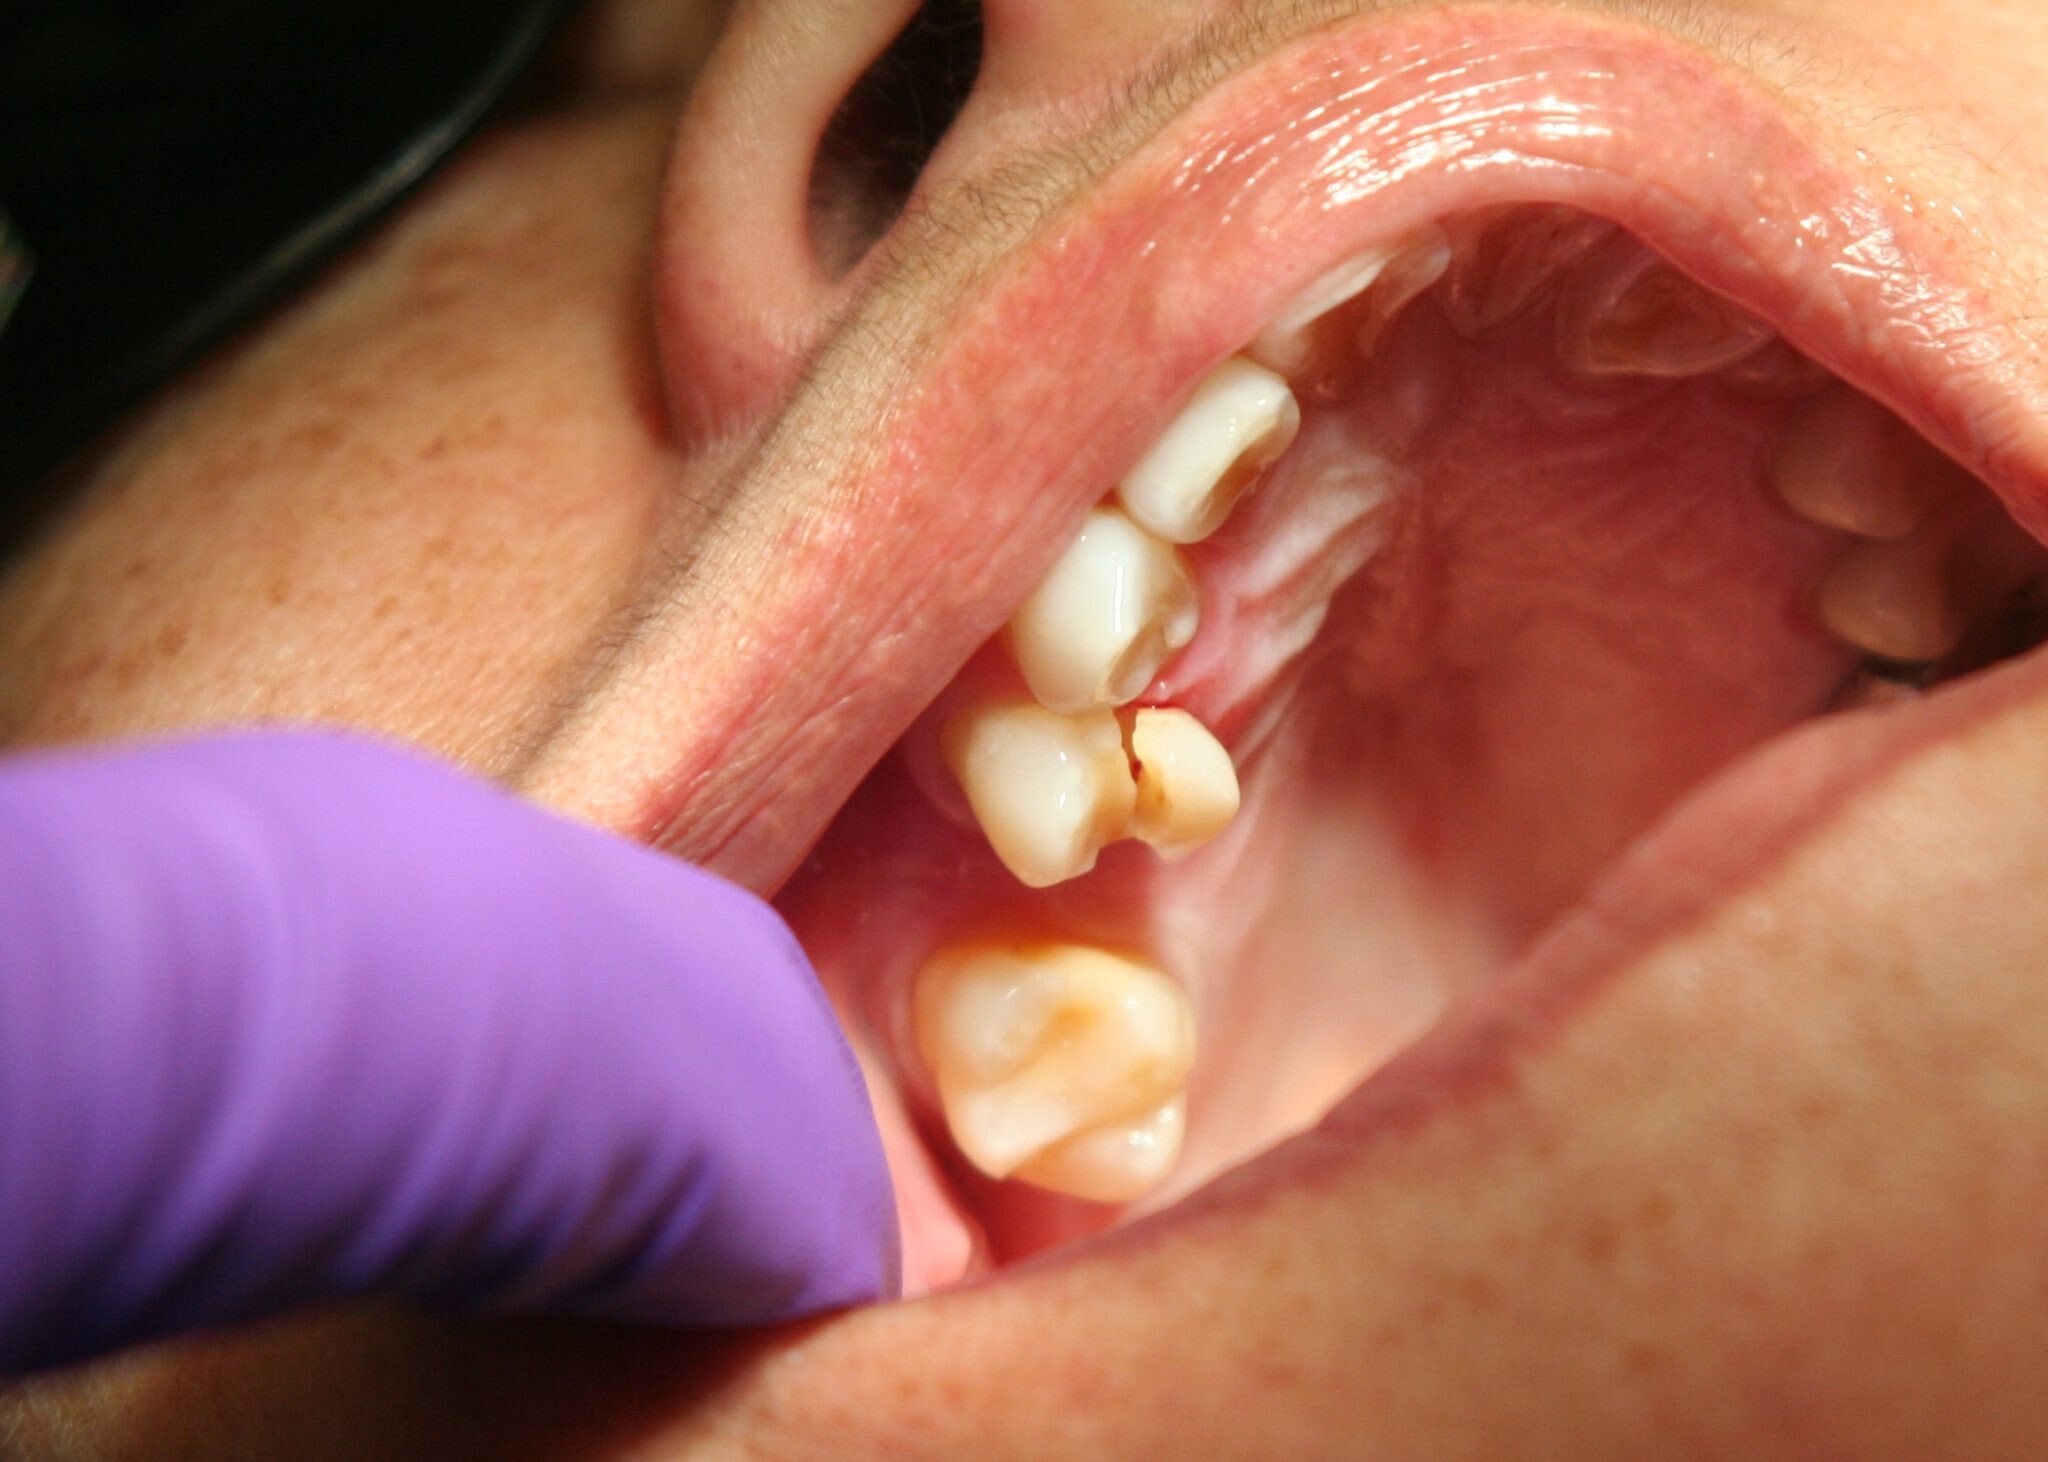

Wisdom teeth promotes Gum Disease

It is a challenging task to clean the area in which the third molars have erupted. Therefore they are at a greater risk of acquiring the periodontal problems. The gum diseases are usually caused by bacteria, and when a tooth can’t be precisely cleaned on a regular basis, the dental plaque gets accumulated around the tooth, which may lead to further complications.

Mutilates the Neighbouring Teeth

Since there is not enough room for the tooth to grow, it will case the teeth to grow in an abnormal manner. This results in impaction of the teeth, giving rise to many other oral problems. When the wisdom tooth emerges against the second set of molar, it might damage them, increasing the risk of acute infection. It will also have an effect on other teeth, which will intensify the need for an orthodontic treatment to align the other teeth.

Tooth Decay

The fully impacted or the partially impacted wisdom teeth are at greater risk of tooth decay, than other teeth. This usually happens, because of the location of the wisdom tooth, especially towards the back of the mouth, which is hard to clean. Moreover, since it lies at the back of the mouth, there are chances of food getting easily trapped between the gums and the tooth, promoting the growth of bacteria.